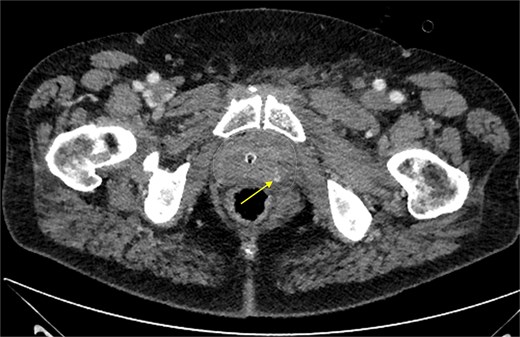

Approximately 6 h after biopsy, the patient was admitted to the emergency department with deterioration, abdominal pain, hypotension, and tachycardia. On arrival, blood pressure was 80/40 mmHg and tachycardia (124 bpm). Laboratory tests revealed leukocytosis (21.9 × 109/l), elevated creatinine (132 μmol/l, eGFR 44 ml/min/1.73 m2), and hemoglobin 6.9 mmol/l. Emergency computed tomography (CT) revealed a large left-sided extraperitoneal hematoma (14 × 11 × 9.5 cm) that displaced the bladder, with capsular venous bleeding but no major arterial source (Figs 2 and 3). Hemodynamic stabilization was achieved with fluid resuscitation and norepinephrine at 0.1 μg/kg/min. Cefotaxime was initiated empirically.

Contrast-enhanced CT scan of the prostate showing focal extravasation in the left dorsolateral midgland, suggesting slow venous oozing. The prostate contour is marked by a dashed line.